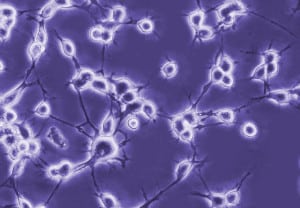

• La utilización de transplantes celulares se encuentra todavía en fase de experimentación en modelos animales.